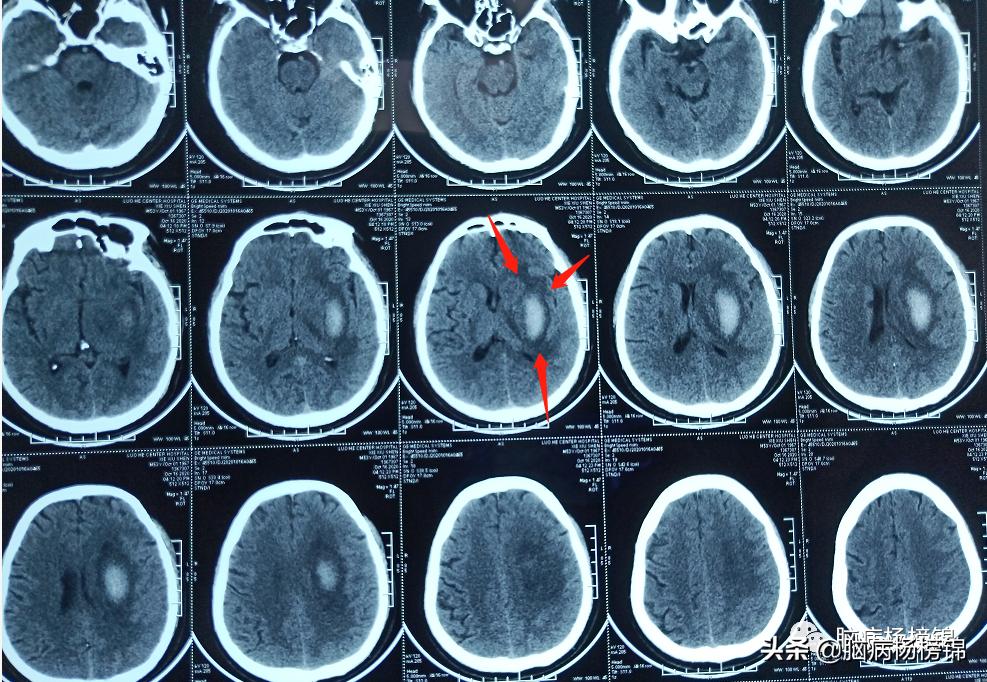

保守治疗25天,血肿大部分吸收。转入漯河六院康复医学科。